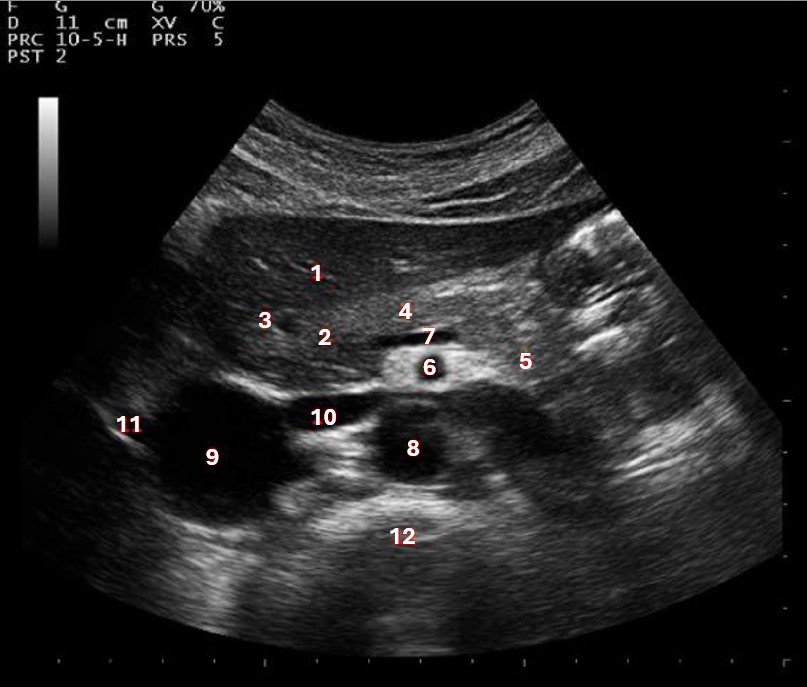

Which of the following structures is labeled #5?

lateral left lobe |

What lobe of the liver is indicated by #1?

posterior right lobe

What structure/vessel is indicated by #8?

medial left lobe |

What lobe of the liver is indicated by #2?

anterior right lobe |

Which of the following structures is labeled #7?

anterior right lobe |

What structure/vessel is indicated by #12?

spine

Which of the following structures is labeled #6?

medial left lobe |

Which of the following structures is labeled #3?

IVC

Which of the following structures is labeled #8?

posterior right lobe |